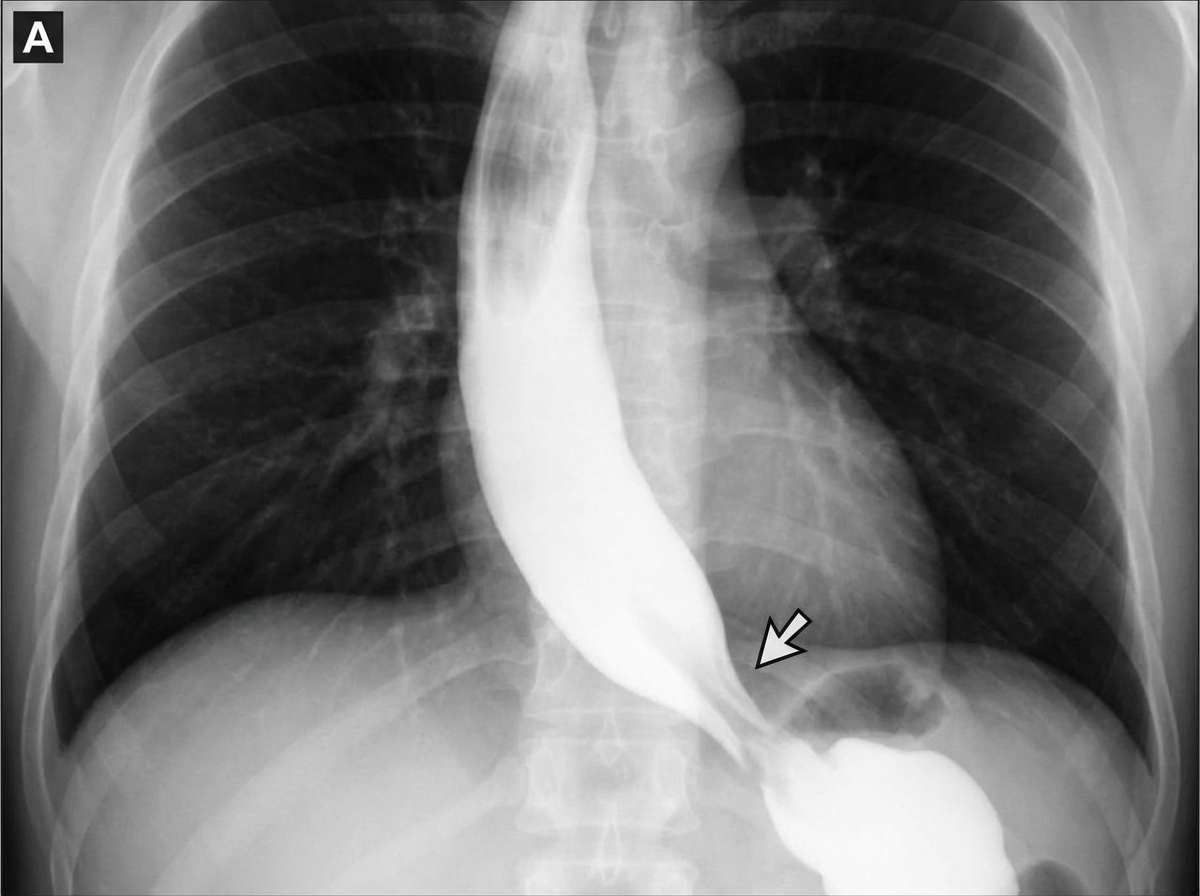

A 45-year-old woman comes to the physician because of progressive difficulty swallowing solids and liquids over the past 4 months. She has lost 4 kg (9 lb) during this period. There is no history of serious illness. She emigrated to the US from Panama 7 years ago. She does not smoke cigarettes or drink alcohol. Cardiopulmonary examination shows a systolic murmur and an S3 gallop. A barium radiograph of the chest is shown. Histopathologic examination of the esophageal wall is most likely to show which of the following?